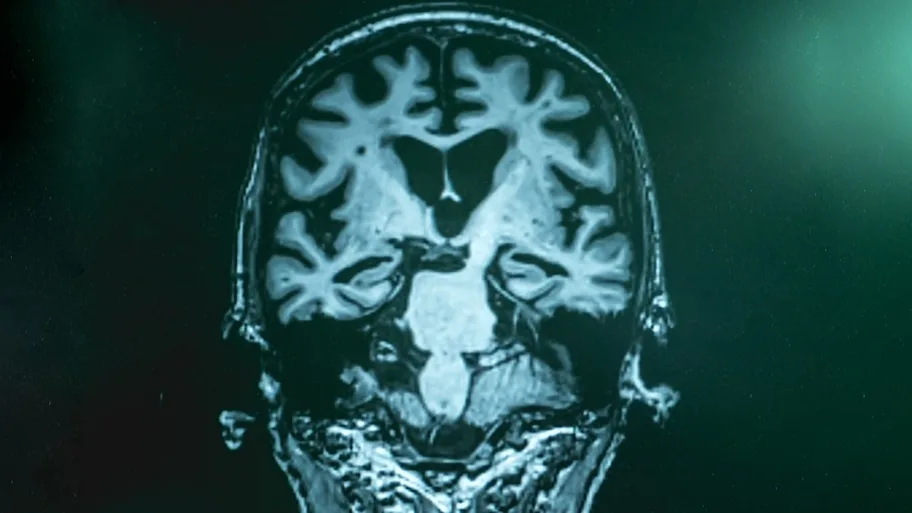

University of Alberta scientists have identified three biomarkers for detecting mild cognitive impairment and Alzheimer’s disease in saliva samples. The research has promising results for application in a clinical setting.

Li and Dixon examined saliva samples from three sets of patients, those with Alzheimer’s disease, those with mild cognitive impairment, and those with normal cognition. Using a powerful mass spectrometer, the pair examined more than 6,000 metabolites–compounds that are part of our body’s metabolic processes–to identify any changes or signatures between groups.